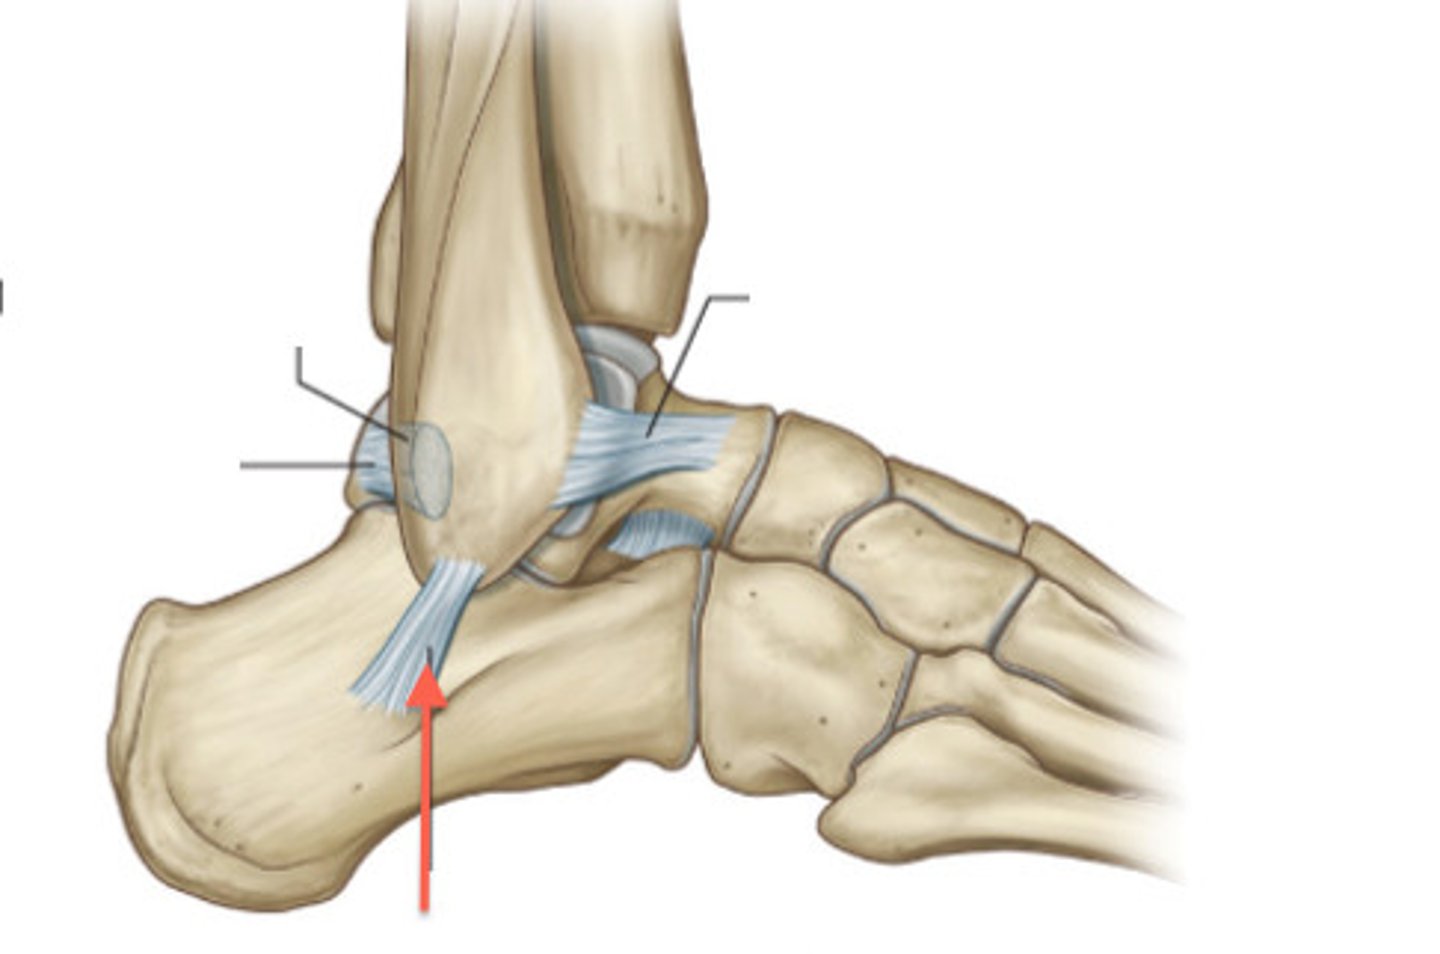

What ligament stabilizes the talus within the mortise joint?

Posterior talofibular ligament

What ligament limits inversion and dorsiflexion?

Calcaneofibular ligament

What ligament limits inversion and plantarflexion?

Anterior talofibular ligament

Most frequently injured ligament in ankle and foot complex

Most common injury mechanism for anterior talofibular ligament sprain

Inversion + plantarflexion during weight bearing

The relative inability of the _______ ________ to block the medial side of mortise joint contributes to anterior talofibular ligament sprains.

Medial malleolus